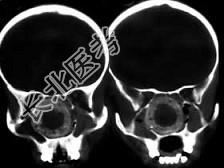

- 单项选择题女,14岁,渐进性鼻塞2年余,右眼肿痛数月,CT如图所示,应诊断为 ( )

A、筛骨骨肉瘤

B、筛骨骨纤维瘤

C、筛骨软骨瘤

D、筛骨结核

E、筛骨骨化性纤维瘤